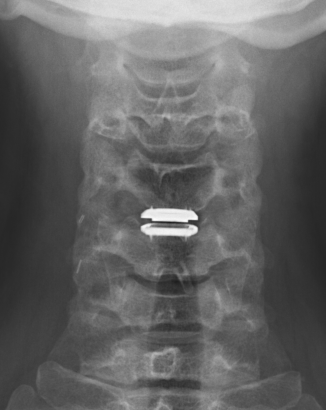

ACDA / Disc replacement

Advantage

Theoretically maintain some motion and preserve other disc segments

Technique

Depuy Discover Medtronic Prestige

Complications

Specific

- anterior displacement

- posterior displacement and spinal cord injury

- subsidence 3% - higher risk if remove or disrupt end plates

- osteolysis

- implant failure

- heterotopic ossification